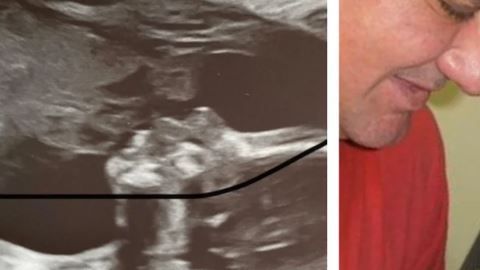

Su padre murió sin conocer a su nieto, pero asegura que se “apareció” en ultrasonido

El parecido es asombroso. Crédito: Reddit

Una joven madre llamada Shantel Marie contó en Reddit una asombrosa experiencia que vivió en el último ultrasonido que se realizó como un chequeo de rutina para saber en qué condición se encuentra el bebé que espera y en donde ocurrió algo que pareciera imposible de creer.

Pero en la imagen obtenida en el ultrasonido, la mujer se percató que en la parte superior izquierda se puede ver claramente un perfil de hombre que mira fijamente al bebé que espera e increíblemente, al hacer la comparación con una foto que le tomó a su padre con su hija, descubrió que eran prácticamente iguales.